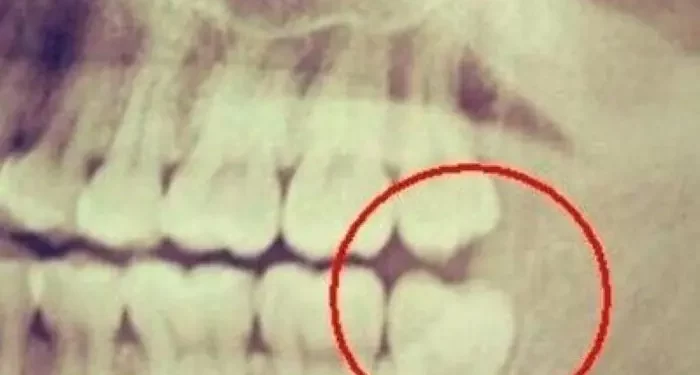

Tooth decay occurs when the enamel, the hard outer layer of the tooth, is eroded by acids produced by bacteria in the mouth. These bacteria feed on sugars from food and drinks, producing acid as a byproduct. Over time, this acid can lead to the demineralization of enamel, resulting in cavities. The process of tooth decay can be broken down into several stages:

Demineralization: The first stage involves the loss of minerals from the enamel due to acid attacks.

Cavity Formation: If demineralization continues without intervention, cavities can form.

Progression: If cavities are not treated, decay can progress deeper into the tooth, affecting the dentin and pulp, leading to pain and infection.